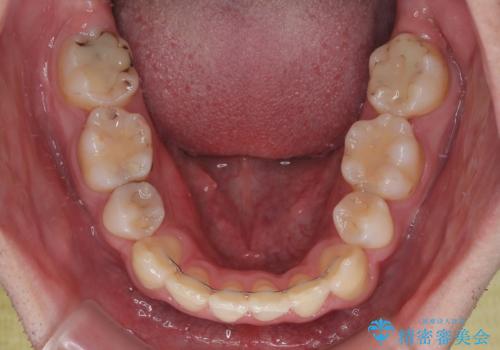

2年半の治療期間を想定しており、予定通りの期間で無事に終了することができました。

唇や顎先に力を入れないなくてもスムーズに唇を閉じることができるようになりました。